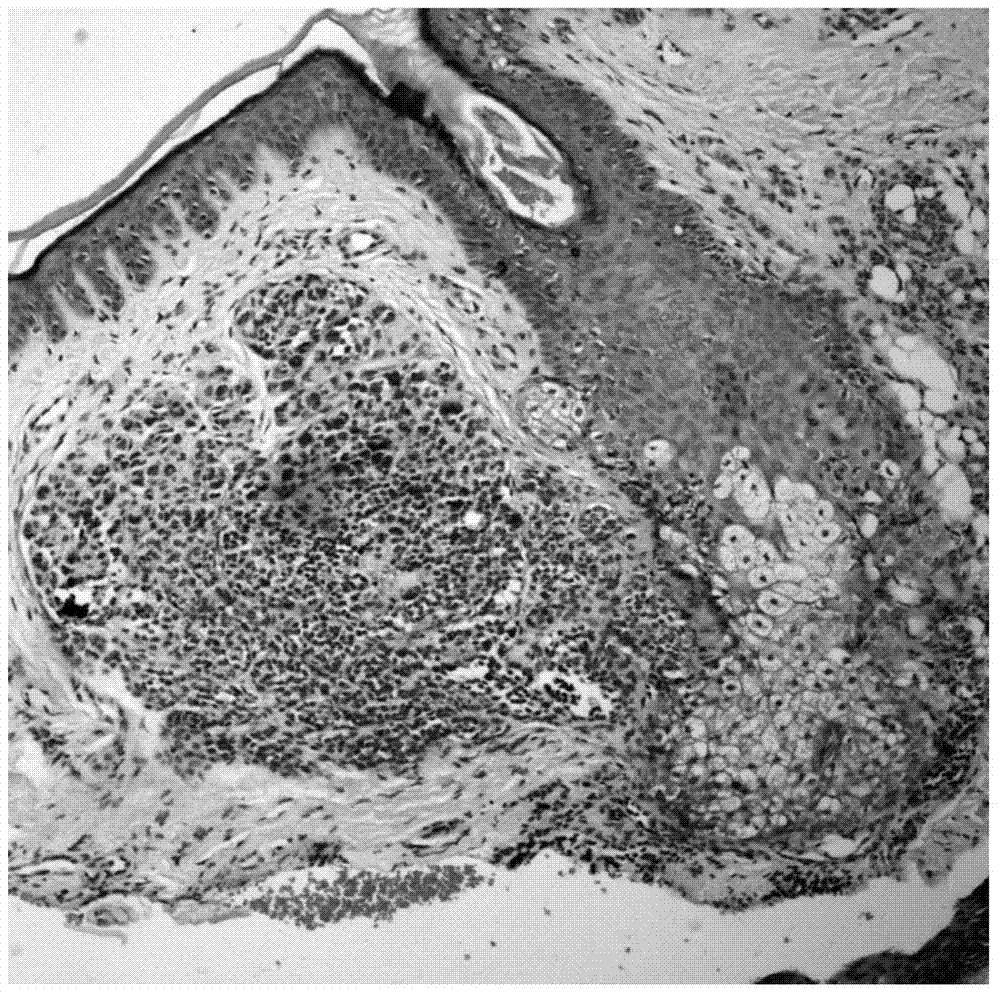

基于深度学习的皮肤活检图像病理特性识别方法